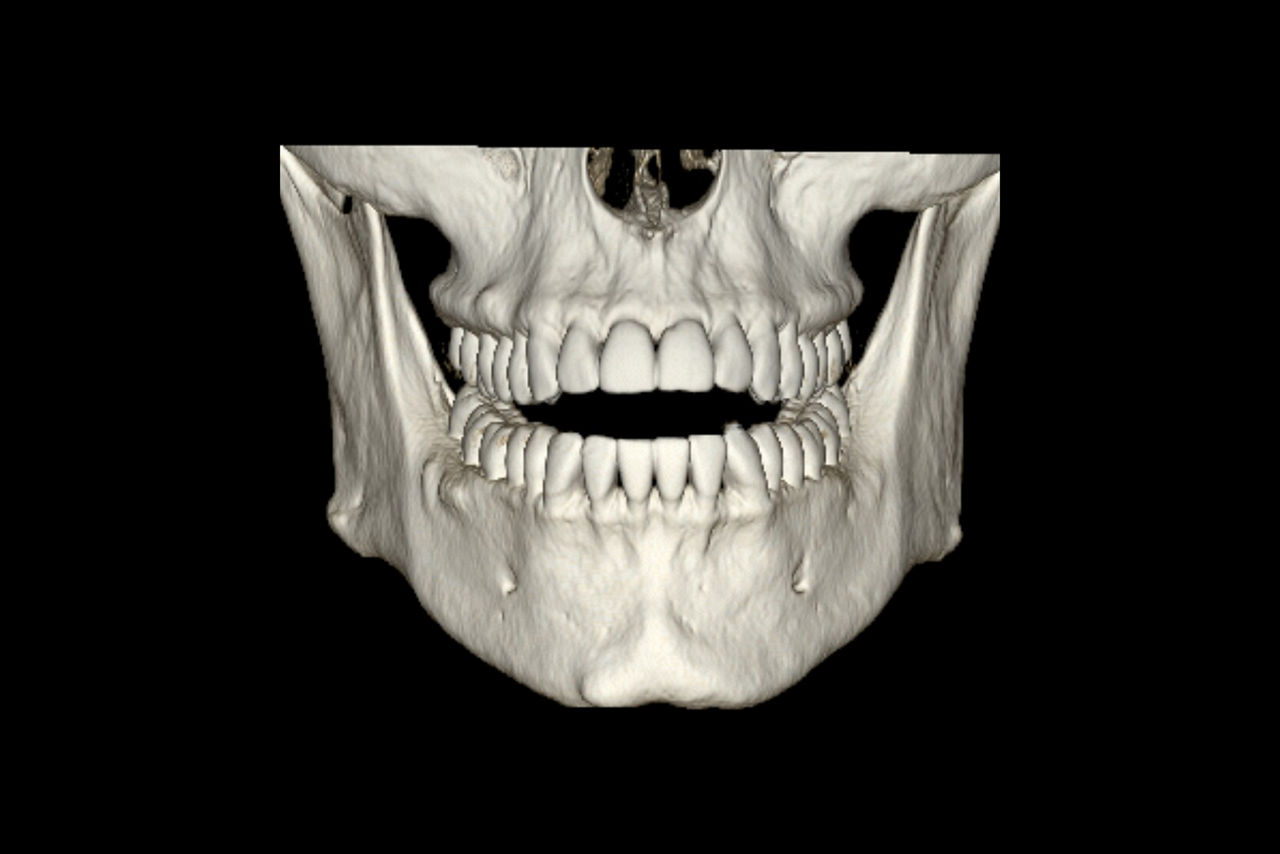

DentaScan

Real-time Oblique and Panorex reformations specific to CT dental imaging.

Panorex and oblique views

• The curve used to generate panorex and oblique views is drawn on selected axial views. It can be adjusted or redrawn easily at any time during Dentascan procedures.

• Axial panorex and oblique views remain cross referenced on the screen. Oblique views are generated in real time when the cursor is moved on axial or panorex views. A similar feature exists when the cursor is moved on a panorex or oblique view.